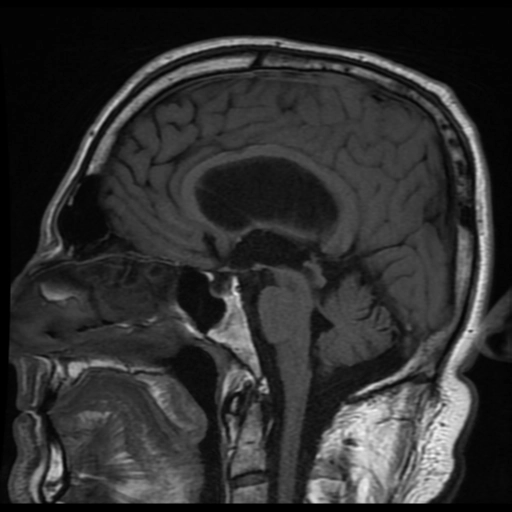

Hẹp cống não (Aqueductal Stenosis)

• Hẹp cống não (Aqueductal Stenosis)